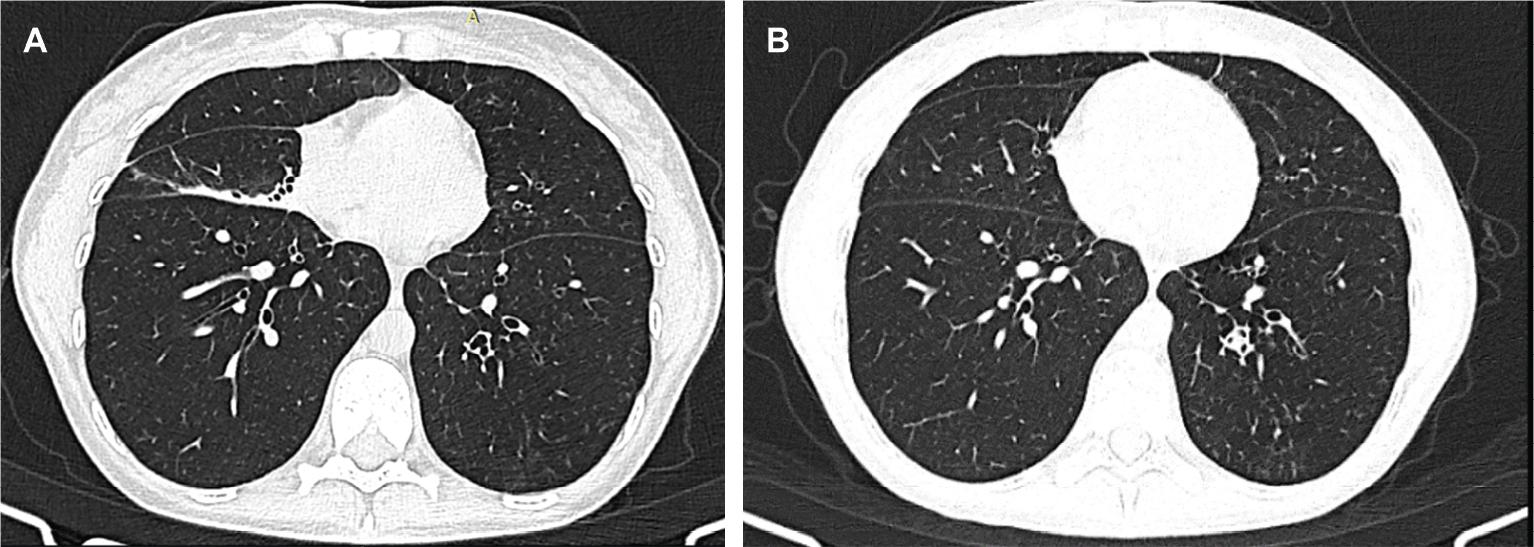

Figure 1.